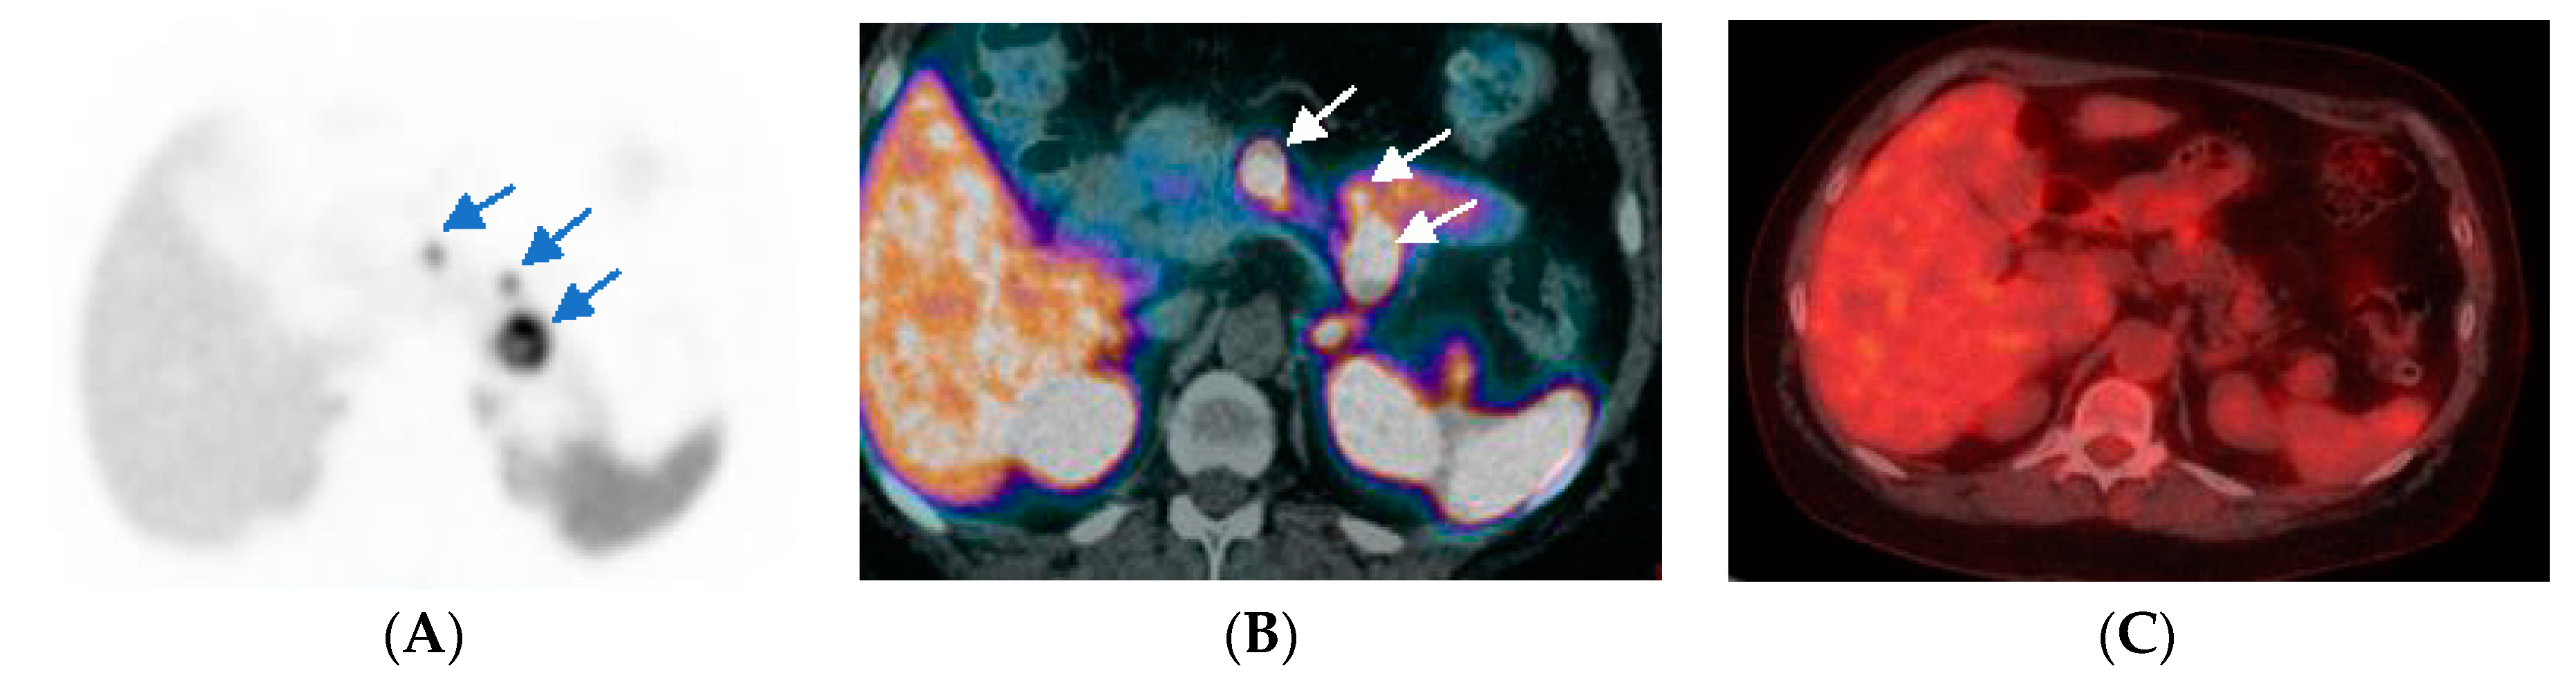

- Kayani, I.; Bomanji, J.B.; Groves, A.; Conway, G.; Gacinovic, S.; Win, T.; Dickson, J.; Caplin, M.; Ell, P.J. Functional imaging of neuroendocrine tumors with combined PET/CT using 68Ga-DOTATATE (DOTA DPhe1,Tyr3octreotate) and 18F-FDG. Cancer 2008, 112, 2447–2455. [Google Scholar] [CrossRef]

- Muffatti, F.; Partelli, S.; Cirocchi, R.; Andreasi, V.; Mapelli, P.; Picchio, M.; Gianolli, L.; Falconi, M. Combined 68Ga-DOTA-peptides and 18F-FDG PET in the diagnostic work-up of neuroendocrine neoplasms (NEN). Clin. Transl. Imaging 2019, 7, 181–188. [Google Scholar] [CrossRef]

- Naswa, N.; Sharma, P.; Gupta, S.K.; Karunanithi, S.; Reddy, R.M.; Patnecha, M.; Lata, S.; Kumar, R.; Malhotra, A.; Bal, C. Dual tracer functional imaging of gastroenteropancreatic neuroendocrine tumors using 68Ga-DOTA-NOC PET-CT and 18F-FDG PET-CT: Competitive or complimentary? Clin. Nucl. Med. 2014, 39, e27–e34. [Google Scholar] [CrossRef]

- Zhang, P.; Yu, J.; Li, J.; Shen, L.; Li, N.; Zhu, H.; Zhai, S.; Zhang, Y.; Yang, Z.; Lu, M. Clinical and Prognostic Value of PET/CT Imaging with Combination of 68Ga-DOTATATE and 18F-FDG in Gastroenteropancreatic Neuroendocrine Neoplasms. Contrast Media. Mol. Imaging 2018, 26, 2340389. [Google Scholar] [CrossRef]